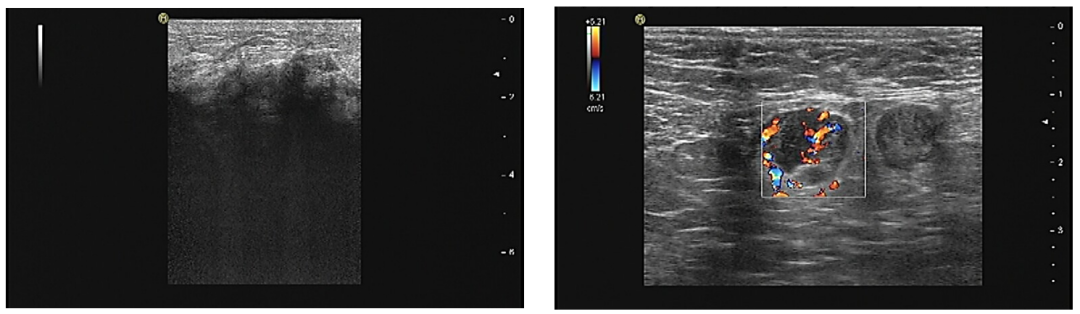

钼靶提示左乳弥漫性增高密度影,边界不清,恶性可能。双腋下未见肿大的淋巴结。BI-RADS 5(图2)。

图2.钼靶(左乳弥漫性增高密度影)